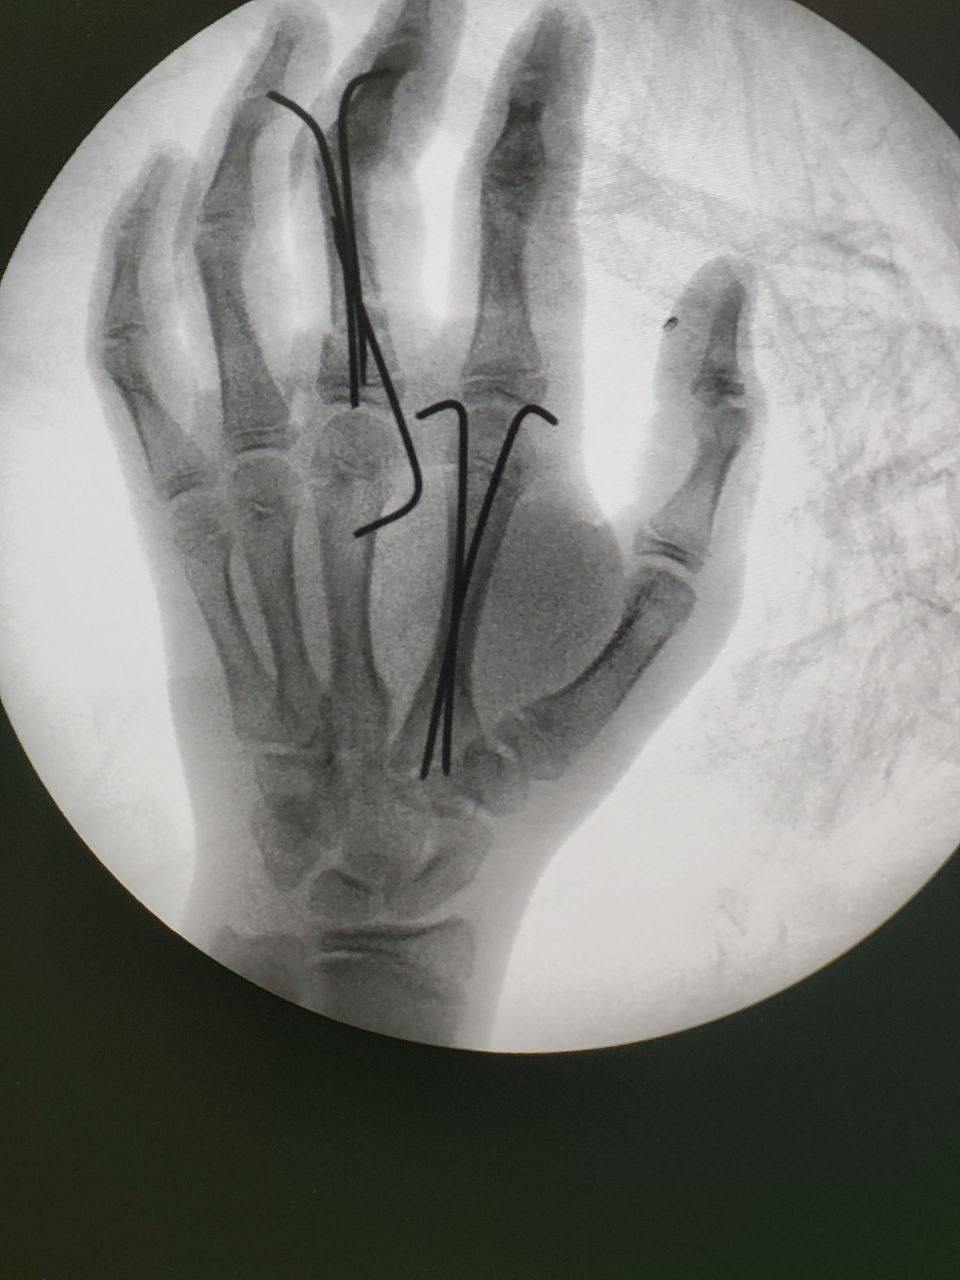

С тяжелой травмой левой кисти был экстренно доставлен 16-летний юноша в Московский областной центр охраны материнства и детства. Подросток неудачно спрыгнул с тарзанки, что привело к открытому оскольчатому перелому среднего и указательного пальцев, а также обширной рваной ране.

— Специалисты оперативно провели хирургическую обработку раны, сопоставили фрагменты кости после перелома и зафиксировали их металлоконструкциями для правильного срастания. Благодаря своевременной помощи удалось избежать серьезных осложнений. Однако пациенту предстоит длительный курс реабилитации для восстановления конечности,— рассказал Александр Григорьев и.о. главного врача МОЦОМД, главный внештатный детский травматолог Московской области.